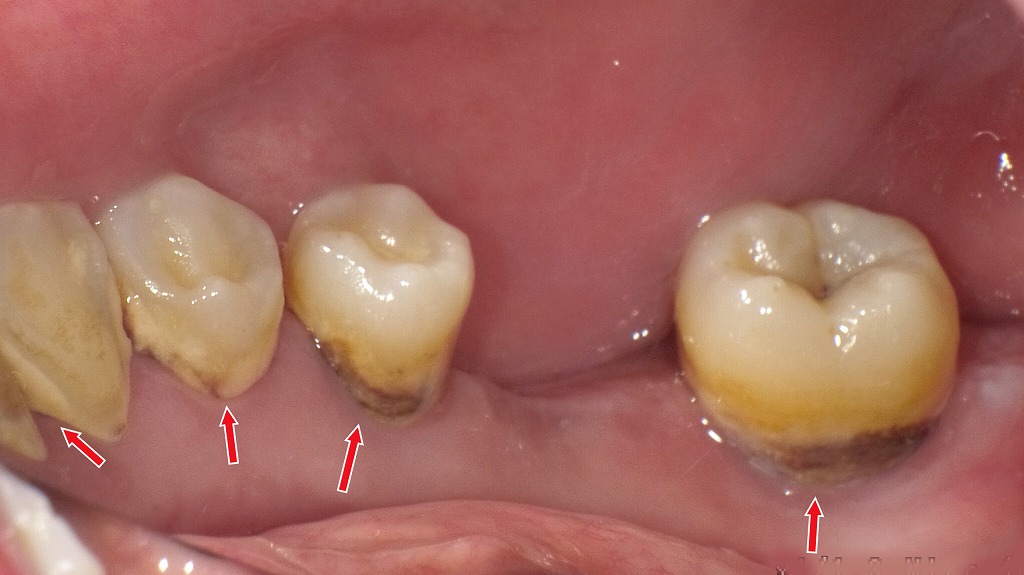

歯ぐき周りに付着した歯石(茶色・黒色の硬い汚れ)は、細菌のすみかとなり、唾液や息が臭う大きな原因になります。歯ブラシでは除去できないため、定期的な歯科クリーニングで徹底的に取り除くことが重要です。放置すると歯周病の悪化にもつながるため、早めのケアが効果的です。

- 🪥 歯石取り・クリーニング:歯磨きで落とせない汚れをプロが除去